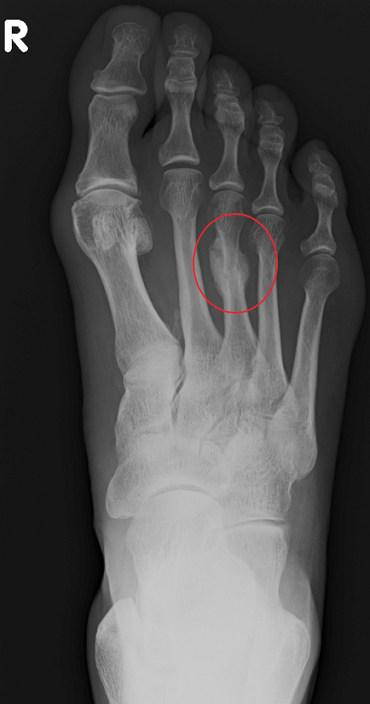

– Tak. To ostatnie, co pan powiedział, jest prawdziwym problemem dla lekarza w pracy z biegaczami. Bo prawdą jest, że nie da się wyleczyć, wygoić złamania zmęczeniowego biegając. Złamanie zmęczeniowe przekształci się w takiej sytuacji w złamanie otwarte. Wtedy sytuacja jest już jasna: jeśli pacjent już zobaczy na zdjęciu rentgenowskim, że kość jest przekrzywiona i pęknięta, to zaczyna się słuchać. Tylko dlaczego tak późno?! Niestety, trzeba zrobić przerwę w treningach i startach. Czasem to oznacza nawet utratę sezonu, to prawda. Ale lepiej stracić sezon, niż trwale utracić zdrowie.

Podsumowując: złamania zmęczeni owe są istotnym problemem wśród biegaczy-amatorów, głównie ze względu na tendencję do ignorowania i bagatelizowania objawów. To powoduje, że duża część tych urazów przychodzi do nas już w stadium bardzo zaawansowanym, a niektóre wymagają już leczenia operacyjnego.